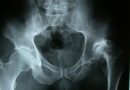

شکستگی مهره های کمری – Broken (Fractured) Low Back Vertebra

این شکستگی زمانی رخ می دهد که یکی از مهره های ستون فقرات شکسته شده باشد. اغلب در اثر آسیب شدید ستون فقرات ایجاد می شود مثل تصادفات اتومبیل، آسیب های ورزشی، و یا افتادن. ولی ممکن است در اثر بیماری هایی مثل پوکی استخوان و یا سرطان هم ایجاد شود. بخش پائینی ستون فقرات بیشتر مستعد شکستگی هاست. در صورت شکستگی در ناحیه ی کمری درد در پائین و بالای کمر، گردن و یا لگن ایجاد می شود. ممکن است ضعف، بی حسی و گزگز هم ایجاد شود.